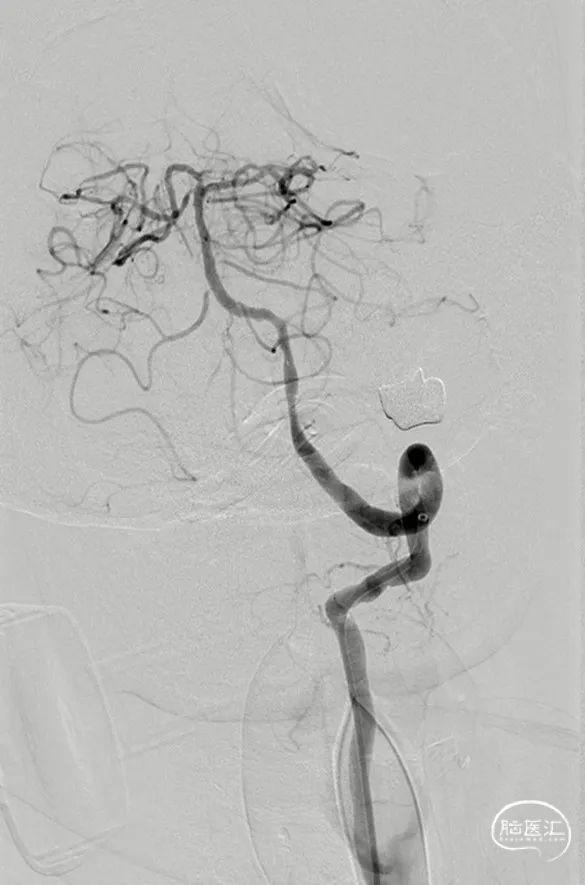

外院DSA(2023.02.09):左侧椎动脉V4段重度狭窄,右侧椎动脉V3段远端闭塞。前循环未见明显异常。

Tethys®中间导引导管沿导丝顺利到达病变近端附近,锁骨下至椎动脉转弯处充分体现了近端良好的⽀撑性与抗折性,帮助后续⾎管开通治疗建⽴稳定通路系统

中间导管到位后造影

复查造影

术前造影

术后造影